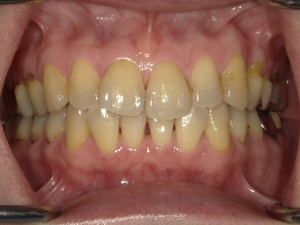

Before After

●ご相談内容:前歯が曲がっている●矯正の種類:マウスピース型「矯正インビザラインGO」●治療期間:18週●治療費用:66万円(税込)